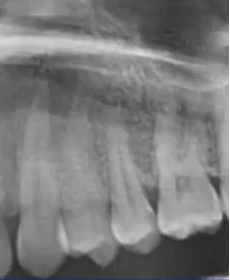

临床检查45叩诊(+),牙颌面见畸形中央尖。加拍根尖片可看到,右下5根方有低密度影,并且右下5的牙根较短小,和曲面断层片上显示的大小不同,所以右下5是舌向倾斜的牙齿。

曲面断层片怎么看口腔精读 | 一次性教你看懂曲面断层片!_https://www.jmylbn.com_新闻资讯_第25张

曲面断层片怎么看口腔精读 | 一次性教你看懂曲面断层片!_https://www.jmylbn.com_新闻资讯_第26张